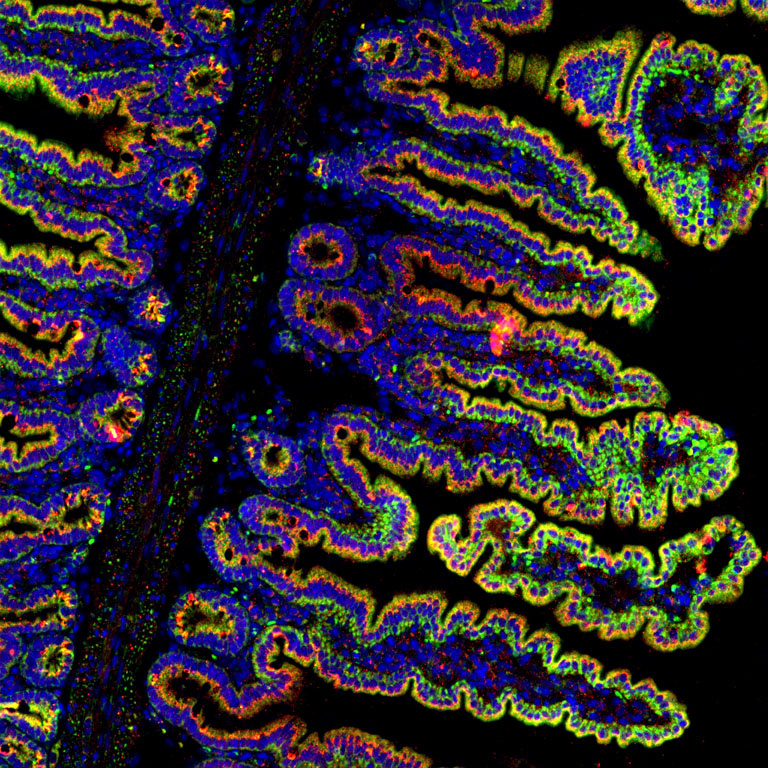

Intestinal crypts and villi from the duodenum of mice with pancreatic ductal adenocarcinoma. This type of cancer enhances intestinal iron absorption in the duodenum, therefore the iron transporter (DMT1) that is stained in red, is increased. The high iron content within intestinal epithelial cells is shown by ferritin staining in green. Nuclei are stained with DAPI in blue. Viewers should note that DMT1 is expressed on the side of the intestine and intestinal epithelial cells facing the lumen, hence the red and yellow staining is only seen on the outside of the intestinal villi.